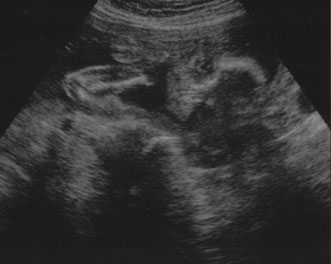

Maternal serum screening can identify pregnant women who are at an increased risk for having a baby with certain birth defects. Patient-specific risks for open spina bifida, Down syndrome and trisomy 18 (Edwards syndrome) (Fig. 1) can be determined by measuring the levels of certain proteins in maternal serum and combining those data with the patient's maternal age and clinical information.10 Women with a positive screen should be offered a definitive diagnostic test.

Fig. 1. Three-dimensional ultrasound showing typical pattern of trisomy 18. A clenched fist with the index finger overlapping the third and fourth fingers is distinctive of this disorder. Image courtesy of GE Medical Systems.